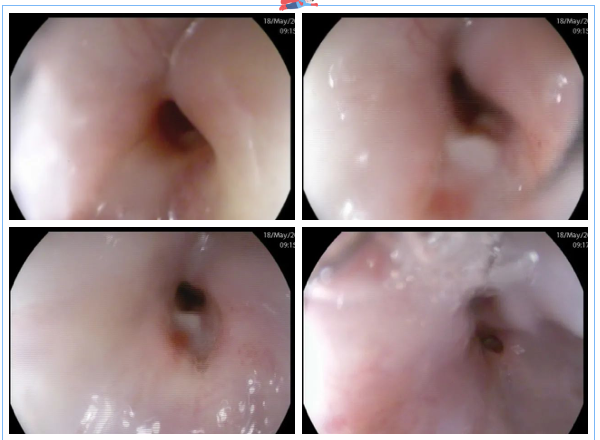

這時,3診是一位懷疑食管瘺的患者,進(jìn)鏡至距門齒約25cm見食管管腔狹窄明顯,無法繼續(xù)進(jìn)鏡,狹窄處黏膜粗糙、色紅,可見潰瘍形成。嘗試給予胃營養(yǎng)管置入,插至距門齒約35cm處阻力過大,反復(fù)嘗試后,無法留置。

同時,7診是一位肝病患者,距門齒約28cm至齒狀線見數(shù)條深藍(lán)色隆起靜脈,扭曲呈結(jié)節(jié)狀,胃體、胃底黏膜充血水腫,呈蛇皮樣改變,散見片狀紅斑。食管靜脈曲張重度,門脈高壓性胃病癥狀明顯。